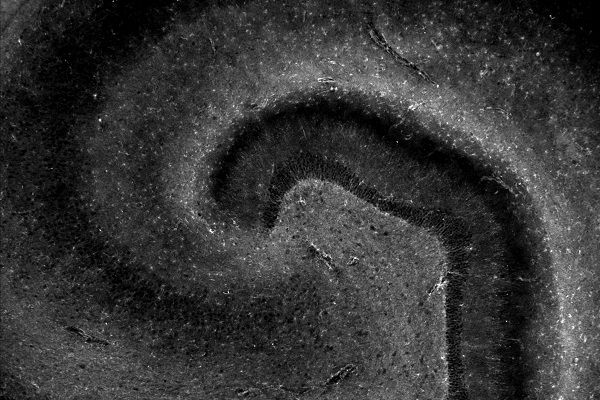

Microscopic photo capturing cells within the hippocampus,

This microscopic photo captures cells within a brain region, the hippocampus, involved with learning and memory. Every lived experience that we are able to remember has boosted the formation of new connections in our brains. These connections are affected in diseases that impair memory, such as Alzheimer's disease. (Art of Research photo by Natalia de Menezes Lyra e Silva)